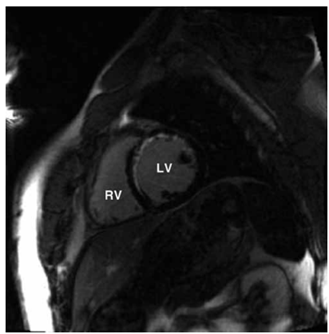

Mulher de 45 anos de idade apresenta quadro de dor torácica intermitente nas últimas seis semanas. Ela tem um forte histórico familiar de doença arterial coronária prematura, mas nenhum outro fator de risco aterosclerótico. O ecocardiograma de exercício atinge a meta de frequência cardíaca desejada e demonstra uma anormalidade focal do movimento da parede anterior do ventrículo esquerdo em repouso, que não foi alterada após exercício máximo. O exame subsequente de ressonância magnética cardíaca é realizado para caracterizar o tecido miocárdico naquela região. Uma imagem tardia obtida após administração intravenosa de gadolínio é mostrada a seguir.

Enunciado 4376907-1

Qual é a causa mais provável da anormalidade do movimento da parede anterior?